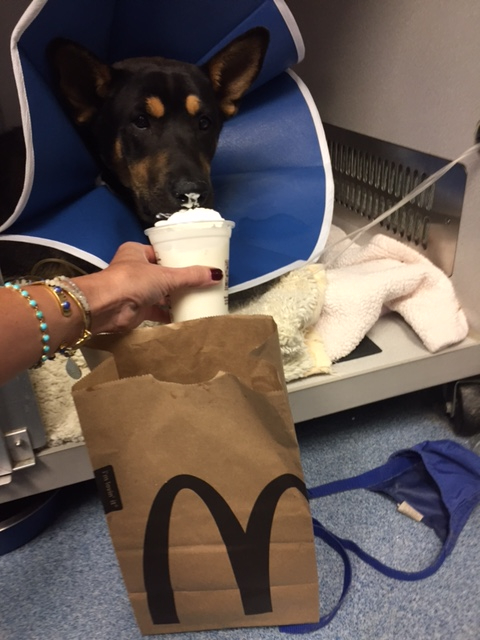

Luckily, a wonderful family found me and paid for my internal bleeding to be controlled and for hospitalization pending possible surgery. However surgery will cost about $10,000.

Then they thought they would set up this GoFundMe page! Please help me- time is running out! I have surgery within the next 3 days!

I am adoptable and can live a full life where I love those who adopt me. I love to lick hands and faces and pat my tail. In fact, there are several families who have expressed interest in me. Please help keep me alive and get the medical care I need by donating money and sharing my story with others.